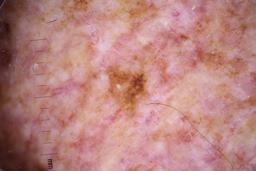

- Name: Challenge 2020: Training

- Number of images: 33,126

- Number of specified lesions: 32,701

- Number of specified patients: 2,056